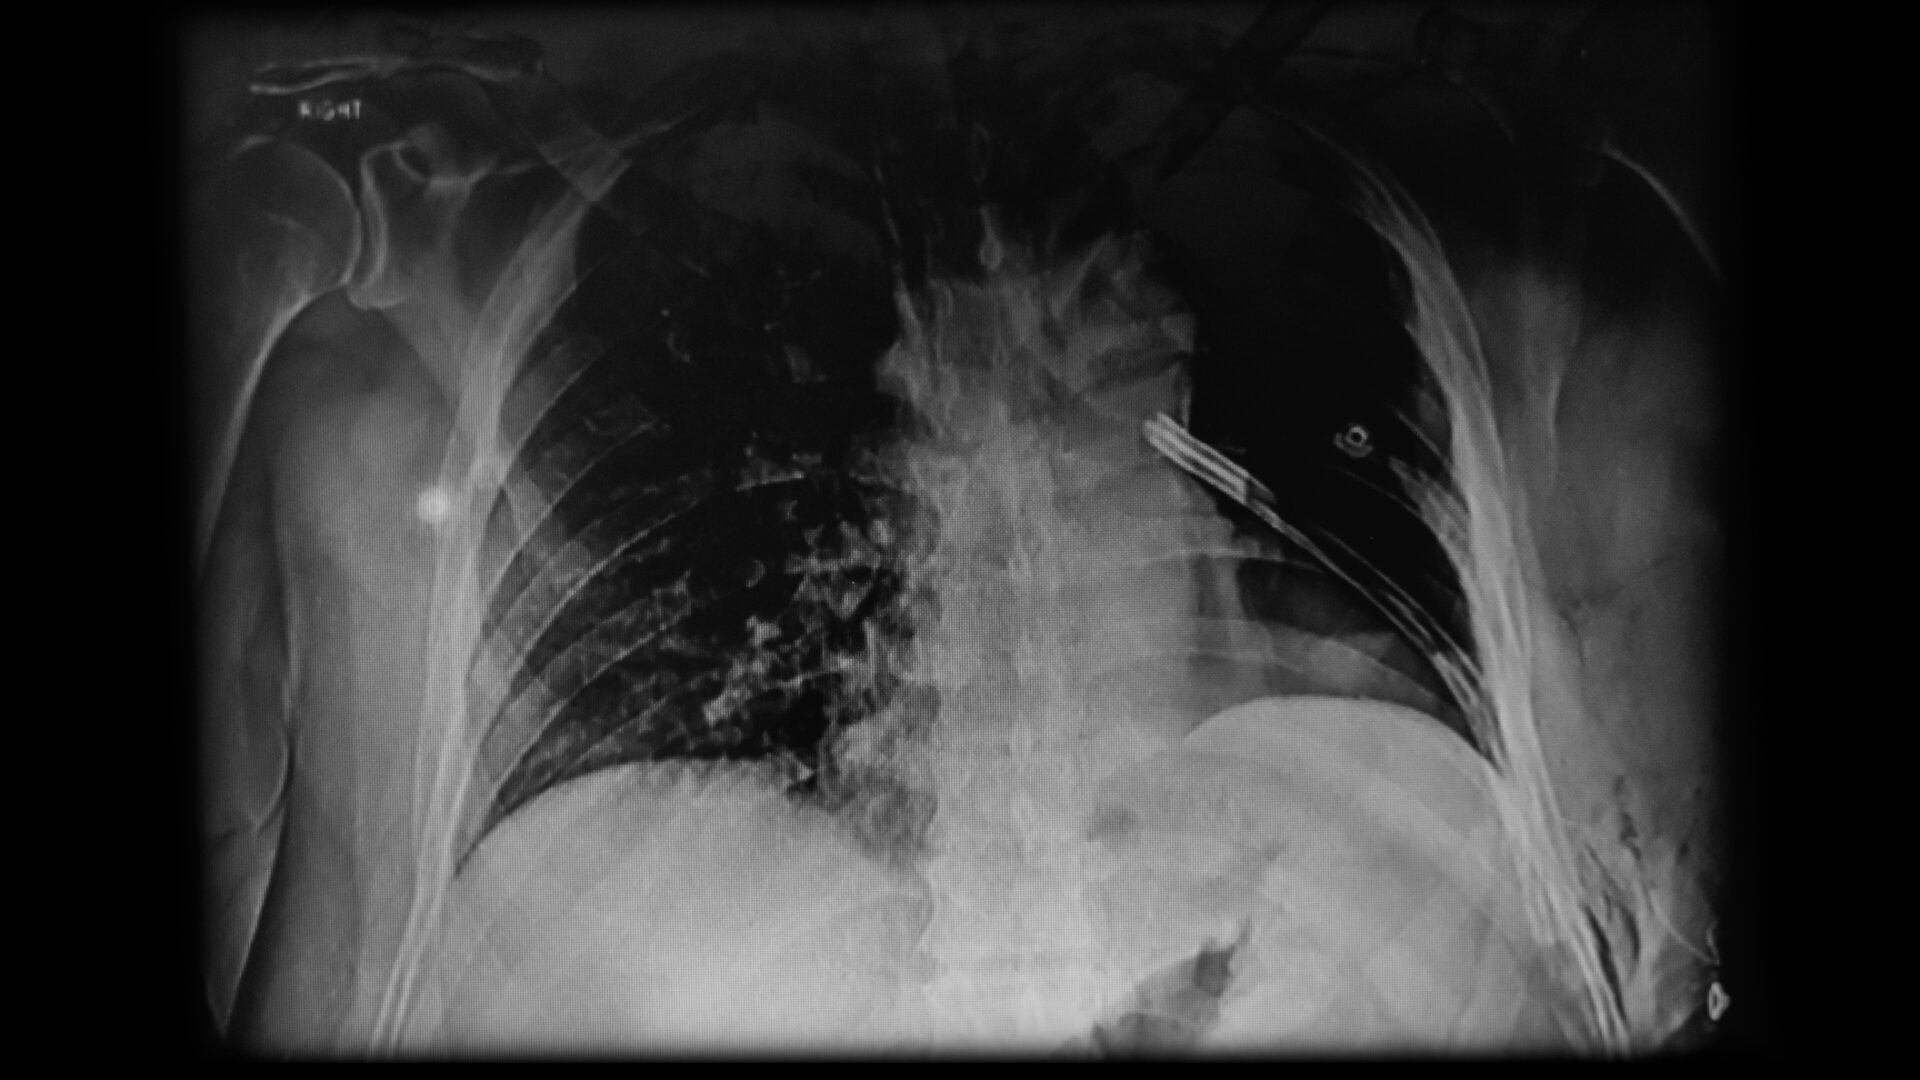

La pose d’un drain thoracique est souvent l’intervention préconisée en radiologie lorsqu’il faut retirer l’air ou le liquide accumulé entre le poumon et la cage thoracique. Seulement, cette procédure envahissante comporte des effets délétères pour le patient, alourdit le travail des soignants et, bien souvent, pourrait être évitée.

Conclusion : 50 à 60 % des drains thoraciques mis aux patients pouvaient être remplacés par une solution moins invasive et moins coûteuse. « L’installation de drains thoraciques était devenue, pour toutes sortes de raisons, une réponse thérapeutique convenue, et cela n’avait jamais été remis en question. Pourtant, la littérature émanant des grands centres dexpertise pleurale en Europe et en Australie suggère de recourir d’emblée aux ponctions pleurales — qui consistent à prélever le liquide ou l’air à l’aide d’une aiguille — et de restreindre l’utilisation de drains à des cas spécifiques », dit le Dr Beaudoin.